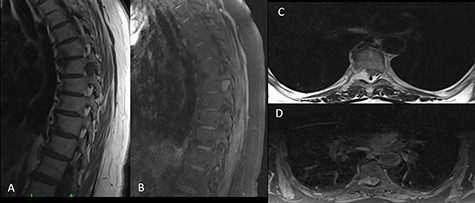

A 65-year-old female patient was admitted to our clinic with the complaints of back pain and progressive weakness in her legs for the last 6 months. An ethics approval and consent to participate were not applicable since the present study is a report about the experiences and observations of medical practices associated with a single individual. On physical examination, the patient had paresthesia and hyperreflexia in both legs.There was no bladder dysfunction or loss of motor strength, while there was bilateral loss of vibratory sense below T8 and moderate loss of pinprick. Bilateral knee clonus and the Babinski sign were negative. Thoracic magnetic resonance imaging (MRI) showed a mass lesion mimicking a meningioma or schwannoma at the foraminal level of the right T7–T8 vertebrae. The tumor was hypointense on T1-weighted images and hyperintense on T2-weighted images in both contrast and noncontrast-enhanced images (Fig. 1). The patient was operated on due to progressive paresthesia and weakness and T7 hemilaminectomy was performed. The dura mater and tumor margins were evident. The transition between tumor tissue and spinal cord tissue was slightly difficult to establish superficially. The tumor tissue was vascular in nature; therefore, the mass was shrunk with bipolar forceps and was completely excised before it was allowed to bleed. No tumor extension was found ventral to the T7 level. Dural leakage developed during tumor excision. Duraplasty was performed by suturing the injured dura and the dura was supplemented with fibrin glue (Tisseel®; Baxter, Newbury, Berkshire, UK).

On preoperative MRI, the mass was (A) hypointense on T1-weighted sagittal images, (B) hyperintense on contrast-enhanced T2-weighted sagittal images, (C) hyperintense on T2-weighted axial images and (D) isointense on T1-weighted axial images.